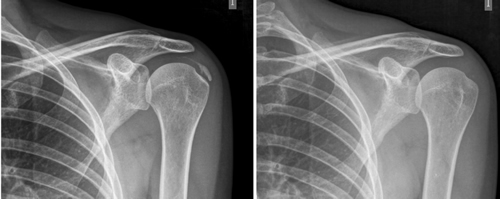

Figura 2

Resultados: Edad media: 54,6 años (n = 138); mujer (73,1 %; n = 101); proporción mujer/hombre 3: 1; tendón supraespinoso (94,6 %; n = 124); subescapular (5,4 %; n = 14); hombro izquierdo (55,1 %; n = 76), hombro derecho (44,9 %; n = 62); bilateral 1,4 % (n = 2); diestros 96,3 % (n = 133); antecedentes personales: tabaquismo (19,5 %; n = 27), diabetes (7,2 %; n = 10). El tiempo de enfermedad promedio fue de 6,08 meses. Dolor agudo-subagudo (menos de 3 meses) 47,1 %; (n = 65), dolor crónico (más de 3 meses) 52,9 % (n = 73). Tipo radiológico: formativo 75,3 % (n = 104), resortivo 24,7 % (n = 34). Número promedio de sesiones: 20. Complicaciones del tratamiento 2,8 % (n = 4): intolerancia/eritema/quemadura. Ocupación: administrativo 39,8 % (n = 55), trabajos manuales 60,2 % (n = 83). El dolor inicial EVA de 7,3 puntos disminuyó significativamente (p = 0,0000) después del tratamiento a 2,7. El tamaño promedio inicial de las calcificaciones fue de 10,7 mm y disminuyó significativamente (p = 0,0000) después del tratamiento a 3,8 mm. Cambio de calcificación: tasa de éxito/curación 55,7 % (n = 77), tasa de mejora 20,2 % (n = 28); tasa de fracaso del 23,9 % (n = 33). La limitación funcional disminuyó de un 10,8 % a un 2,1 %.

Results: Mean age 54.6 years (n = 138). Female (73.1 %; n = 101); female to male ratio 3:1. Supraspinatus tendon (94.6 %; n = 124), subscapularis (5.4 %; n=14); left shoulder (55.1 %; n = 76), right shoulder (44.9 %; n = 62). Bilateral 1.4 % (n = 2). Right handed 96.3 % (n = 133); Personal history: smoking (19.5 %; n = 27), diabetes (7.2 %; n = 10); disease time averaged 6.08 months; acute-subacute pain (less than 3 months) 47.1; (n = 65), chronic pain (greater than 3 months) 52.9 % (n = 73). Radiological type: formative 75.3 % (n = 104); resorptive 24.7 % (n = 34). Average number of sessions: 20.5. Treatment complications 2.8 % (n = 4): intolerance/erythema/burn. Occupation: administrative 39.8 % (n = 55), manual jobs 60.2 % (n = 83).

Average initial pain 7.3 points (VAS scale), significantly decreased (p = 0.0000) post treatment to 2.7. Initial average size of calcifications 10.7 mm and significantly decreased (p = 0.0000) post treatment to 3.8 mm. Change of calcification: success/cure rate 55.7 % (n = 77), improvement rate 20.2 % (n = 28); failure rate 23.9 % (n = 33). Functional limitation decreased from 10.8 % of patients to 2.1 %.